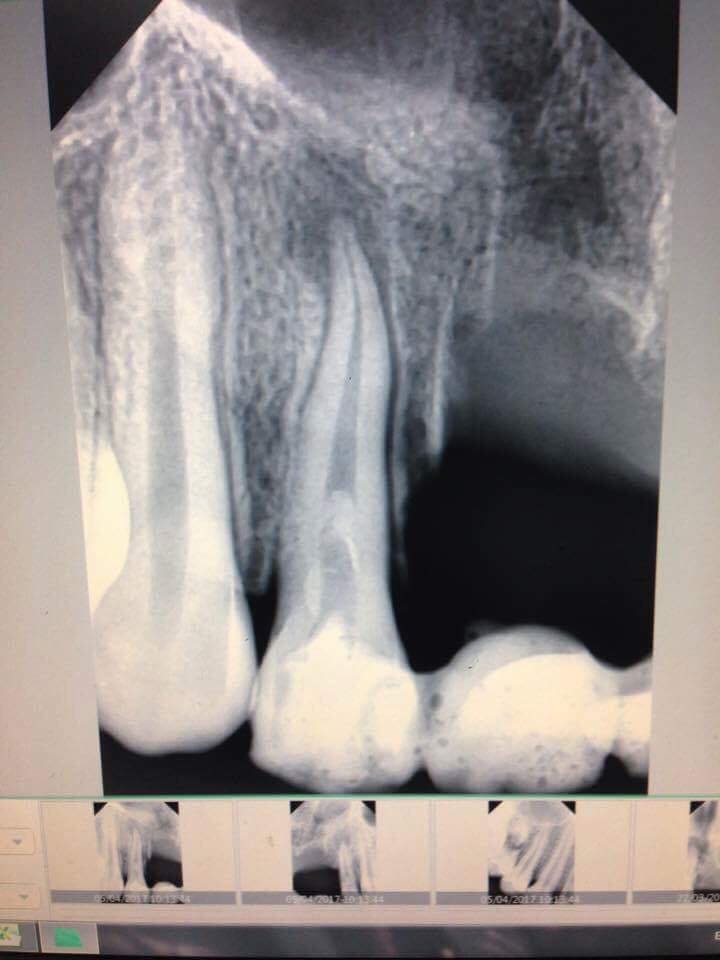

Việc cho Arsenic vào ống tuỷ khi nội nha là một việc làm nguy hiểm. Vì nếu để Arsenic rò rĩ ra ngoài thì việc gây nên hoại tử nha chu và xương là chuyện thường gặp .

Bên cạnh đấy nếu để Arsenic vào ống tuỷ có nguy cơ gây nên các trường hợp viêm quanh chóp sau đó, đặc biệt nguy hiểm với các ống tuỷ lớn và có lỗ chóp mở rộng.